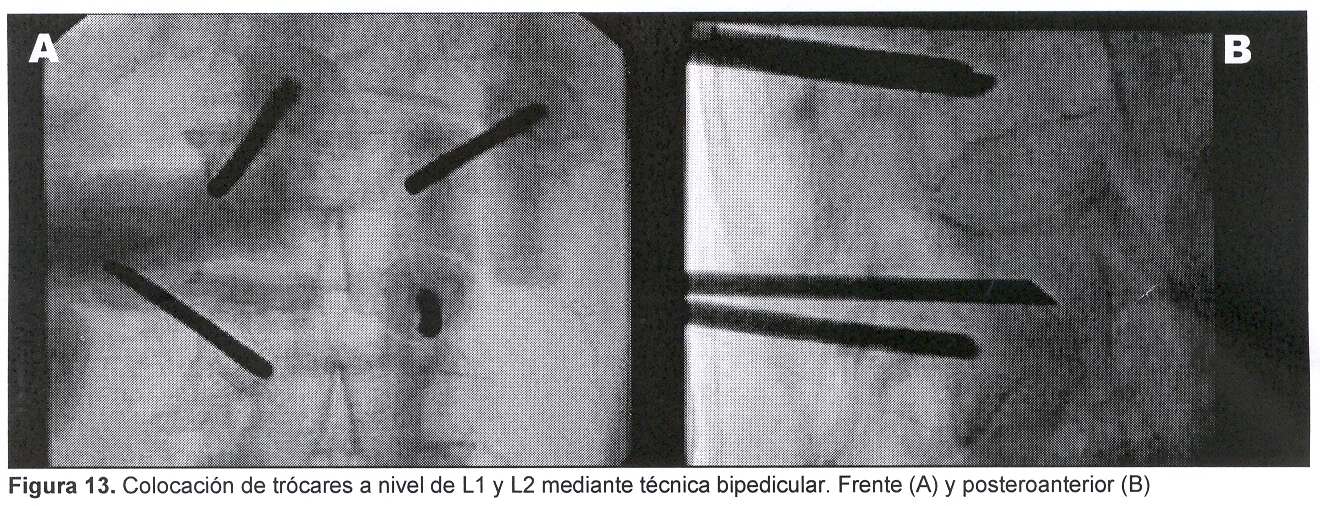

Sexo femenino, 67 años, con dolor raquídeo dorsolumbar de varios meses de evolución. En los últimos 15 días nota aumento de la intensidad del dolor, que la obliga a mantener reposo en cama en forma permanente a pesar del tratamiento médico. Sin sintomatología radicular. Se realizó radiografía y TC de región dorsolumbar que mostró: desmielinización difusa y fractura por aplastamiento de L1 y L2 con disrupción parcial de los muros posteriores.

La paciente es tratada en forma ambulatoria (figuras 13 y 14), a las 12 horas del procedimiento el dolor raquídeo comenzó a disminuir para desaparecer completamente a la semana.